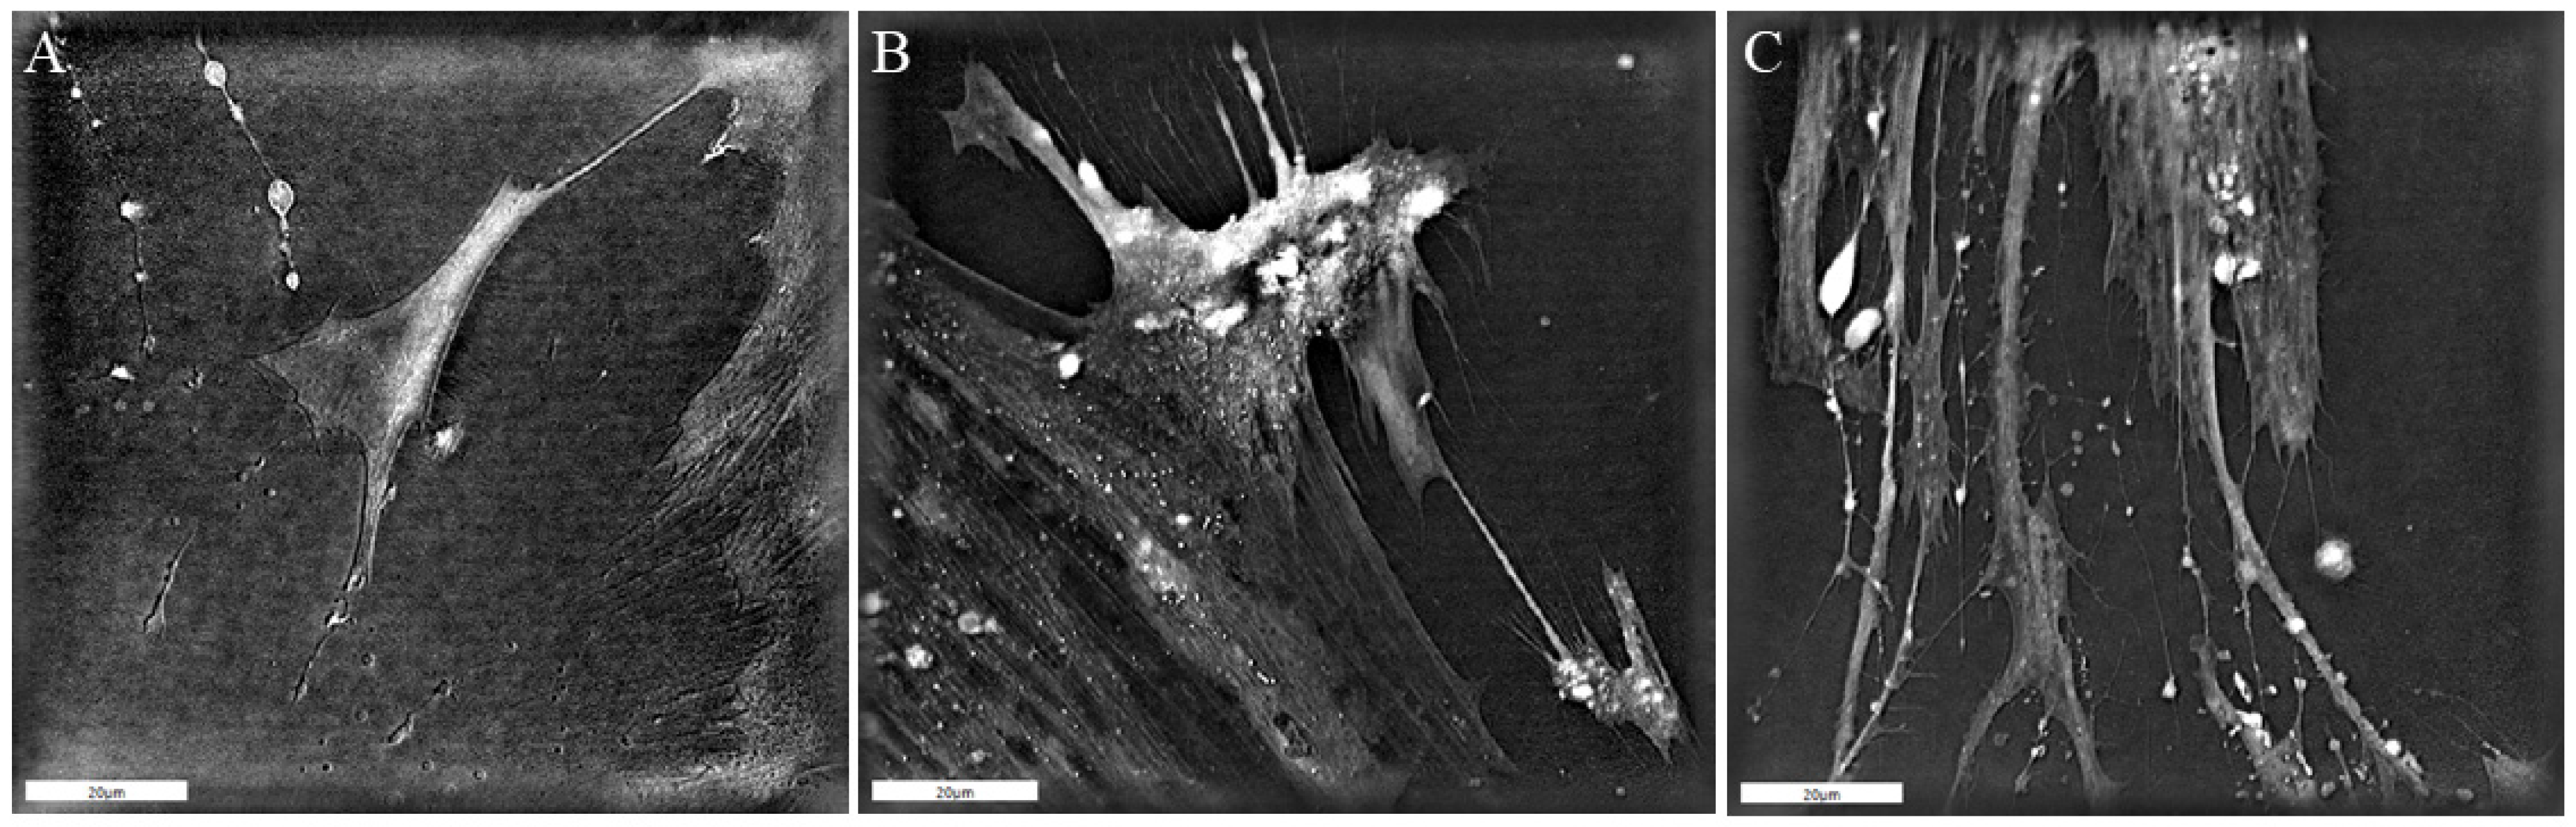

2.5. Three-Dimensional Holotomographic Microscopy

3.2. Patient-Derived CAF Behavior and the Potential to Influence Tumor Cell Growth in HNSCC